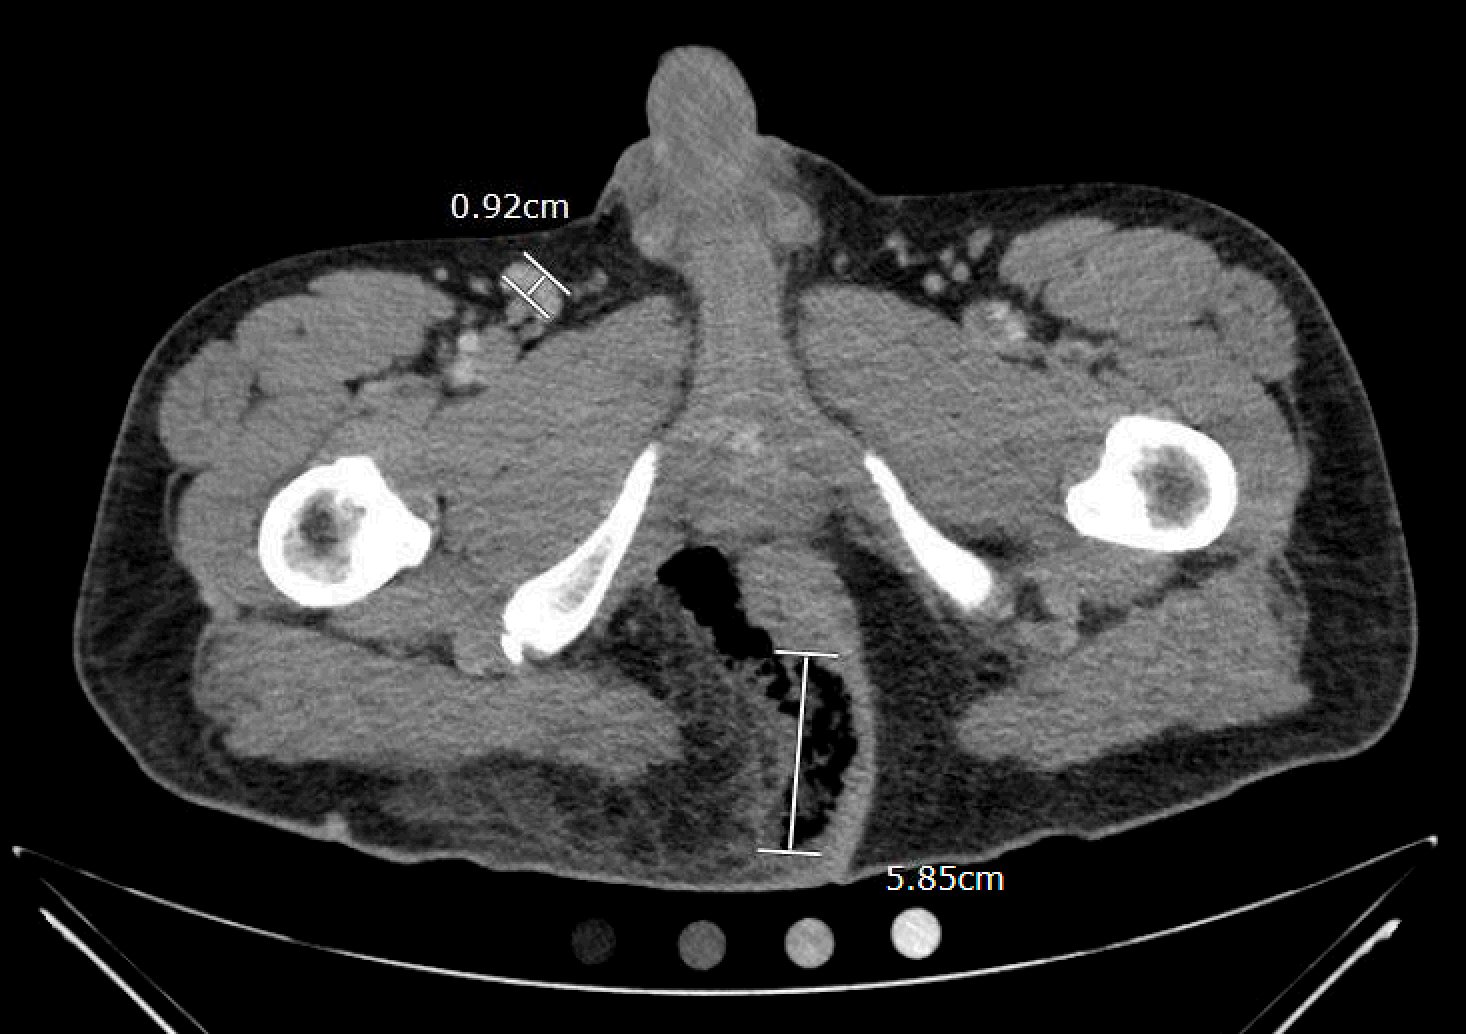

The computed tomography (CT) of the abdomen and pelvis revealed significant subcutaneous gas tracking along the perineum and right gluteal region (orange outline) into the scrotum with associated scrotal edema (yellow arrow) and subcutaneous inflammatory fat stranding of 0.92 cm (red arrow) consistent with Fournier’s gangrene. There is early fluid loculation along the right medial gluteal cleft of 5.85 cm (green arrow) without a sizeable drainable abscess seen.